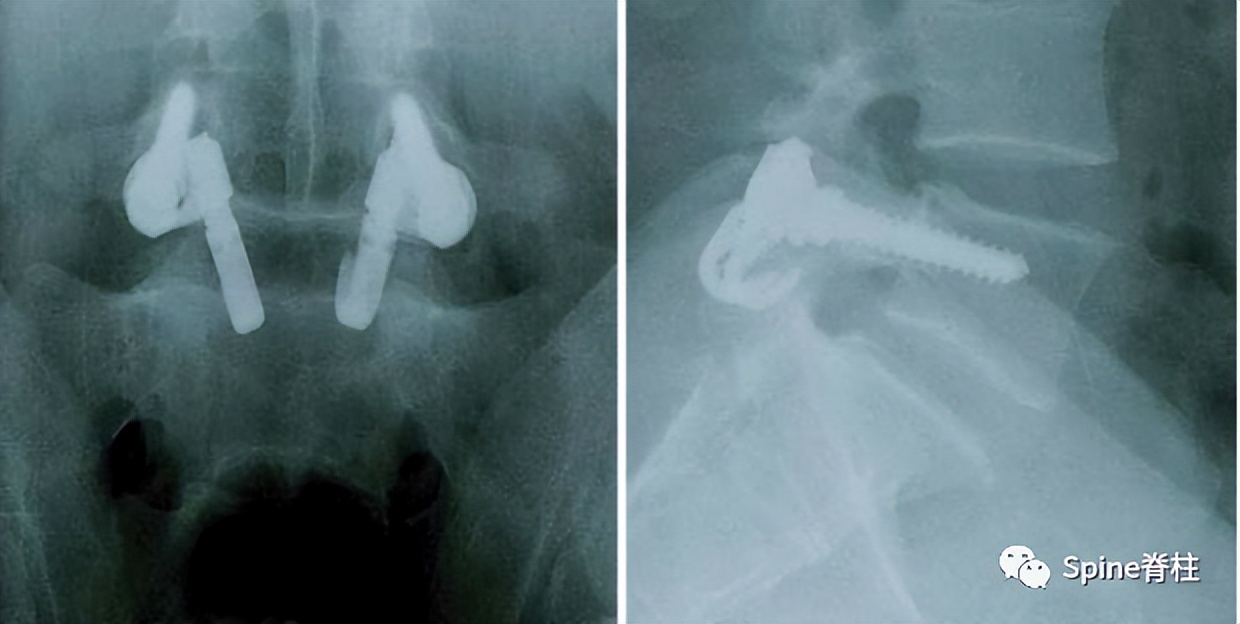

随着内固定的发展,既往峡部单纯修复植骨因融合率低、卧床时间长,现已很少应用。而植骨修复并节段固定有多种方法,包括Scott接线法、Buck螺钉法、Louis的蝶形板、钉钩技术(椎弓根螺钉和钩-棒系统)、U形棒等。从临床角度看,钉钩技术可以用刚性植入物固定断裂的峡部,并沿椎板方向施加作用力,有效稳定峡部,这对于达到更好的骨性愈合是至关重要的。理论上,此种方法更符合生物力学,对邻近节段影响小,但应把握好适应症,建议单纯腰椎峡部裂伴或不伴轻度滑脱患者可行植骨修复并节段固定。

1. 椎弓根螺钉-钉钩系统

PMID: 9199377

PMID: 15699811

PMID: 17520298